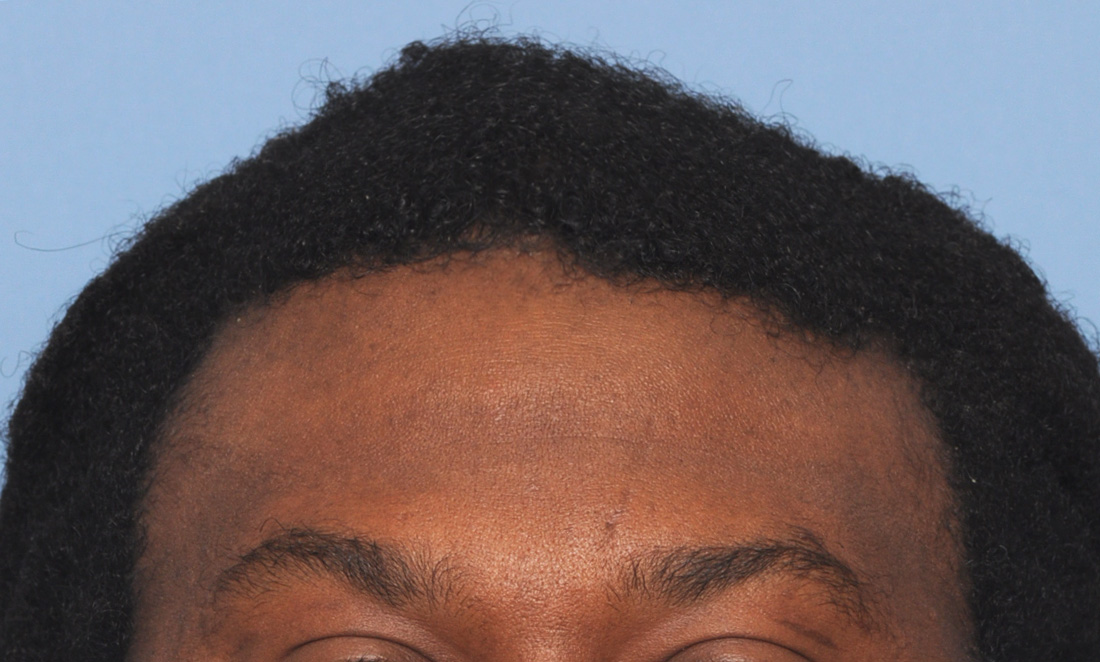

Patient 4

Desire for an improved head shape so that it looks rounder and not so peaked or sloped.

Placement of custom skull implant for parasagittal augmentation to create a rounder head shape. An example of what appears to be a high sagittal crest that is really low parasagittal skull areas.

Desire for an improved head shape so that it looks rounder and not so peaked or sloped.

Placement of custom skull implant for parasagittal augmentation to create a rounder head shape. An example of what appears to be a high sagittal crest that is really low parasagittal skull areas.